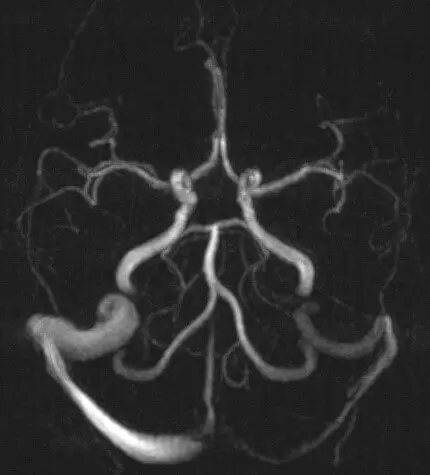

На МРТ снимках приведены анатомические варианты недоразвития сосудов мозга, что может сопровождаться вегетососудистой дистонией.

Для диагностики ВСД используют несколько методов. Для уточнения состояния мозга используют МРТ головы и головного мозга (одно исследование). Современные МРТ–аппараты позволяют увидеть изменения в самой ткани мозга, определить обратимость изменений, наличие дисциркуляторной энцефалопатии, своевременно выявить начальные изменения, на которые нужно срочно реагировать. Чаще такие изменения происходят в участках головного мозга с исходно измененным кровотоком или ликворотоком (два взаимосвязанных процесса). Поэтому одновременно с МРТ самого голоного мозга проводят МРТ исследование сосудов головного мозга с использованием специальных режимов. Это исследование называется МРТ реконструкция сосудов головы.

Удобно для доктора и безопасно для пациента то, что можно исследовать сосуды без введения контраста. Исследование сосудов мозга крайне важно при диагностике причин вегетососудистой дистонии (ВСД). Такое исследование позволяет определить области мозга с исходным дефицитом кровотока. Это участки мозга лежат в зоне риска поскольку ввиду исходной недостаточности кровоснабжения.

В стандарт исследований мозга в Центре «Меддиагностика» входят суперсовременные режимы МРТ обследования: M-Power, технологии Advanced Non-Contrast MRI и др. Эти режимы позволяют выявить дефекты кровотока даже при отсутствии явных клинических проявлений.